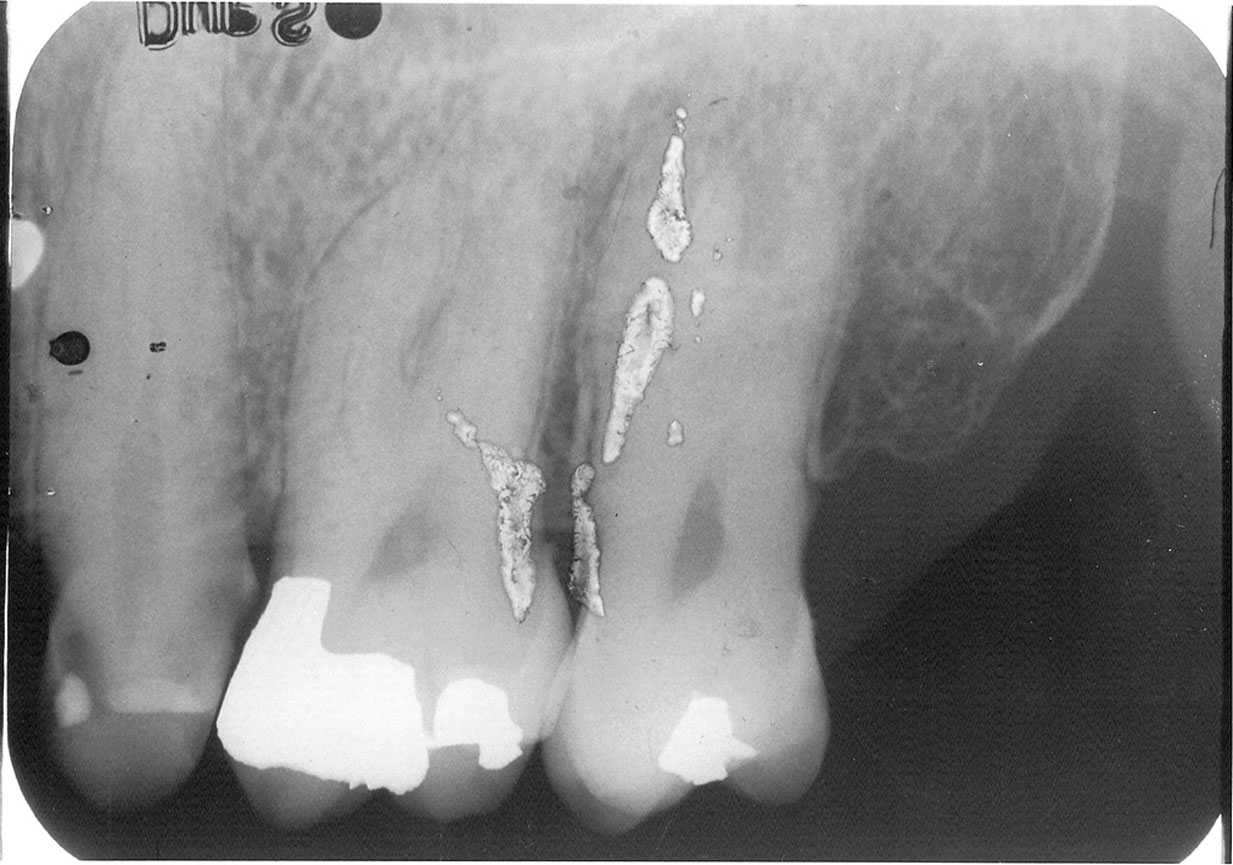

Static Electric Discharge

Damage from static electricity usually occurs as the film is prepared for processing. The synthetic material in some office fabrics can cause a static discharge to jump to the film, particularly when the darkroom humidity is low. Protective latex gloves can cause static electricity that produces a black, smudge-like image. Usually however, the damage is done as the film comes out of the packet and friction between sliding components generates a static charge sufficient to energize the silver bromide emulsion. The resulting artifact appears as radiolucent lines and/or areas, often with a “tree-like” configuration, as in Figure 12. Static electricity can also cause a localized overexposure.

Remedy: The operator should slowly remove the film from the film packet. The dental office also can operate a humidifier in areas where it is very dry.

Figure 12. Static electrical discharge.

Figure 12